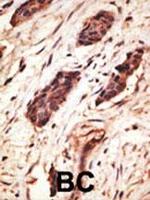

WB IHC (P) ICC/IF ELISA

WB IHC (P)

IHC (P) ICC/IF